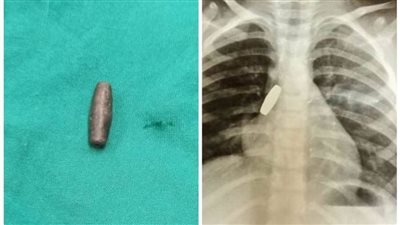

طلقة

مستشفى ملوي التخصصي ينجح في إنقاذ طفلة ابتلعت رصاصة